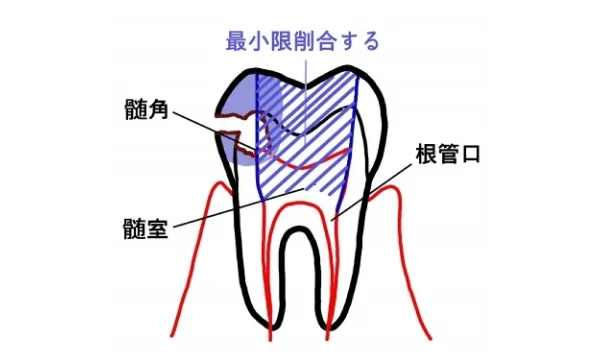

う蝕治療では、細菌がいなくなるまで歯質を取り除いていく必要があります。取り切ると神経まで穴が開いてしまう疑いがある場合は、あえてう蝕を残して特殊な抗生剤と歯質保護薬剤を使用して1年弱待ちます。その後、神経表面に歯質が厚くなるのを待って、取り残したう蝕を取り切ります。 こうして、う蝕をとったら樹脂で歯質をコーティングし、失った歯質を補填します。この状態で次回までに痛まないか確認します。これは、削り取る刺激で神経に炎症が起きるからです。少ししみることはありますが、尾を引かないようならば神経は残せると判断します。

口の中の唾液が修復する部分につくとうまくつかなくなってしまうので、唾液を排除します。歯の表面に接着剤のぬれが良くなる処理をして液状の接着剤を流して固めます。樹脂を歯の形に整えながら充填します。最終的な歯の形に削合して研磨します。 これがう蝕で神経の治療にならなかった場合の治療手順です。治療は歯を削るにしても最小限削るのが理想的です。 う蝕・虫歯の治療は、まさに歯の形を元に近い形に修復しているものです。虫歯の原因が改善されなければ、また同じように虫歯になってしまいます。形が治ると安心してしまう患者さんも多いのですが、リスクと向かい合い予防することが大切です。

神経をとる治療

不幸にして神経をとらなければならなくなった場合は、神経が回復不可能、つまり死ぬ方向に進んでしまった場合に行います。まず、健全な歯の部分はなるべく削らず、更に根の治療が効率的に出来るように形成します。すると神経の上の部分がまず露出します。この部分は髄室といいます。 この部分の神経をしっかりとれるように角の部分(髄角)までしっかり形を作ります。その後、その下にある根の部分の神経の入り口(根管口)を探します。歯の種類に種類によって大まかな数は決まっていますが実際にはそれより多いことが多いので顕微鏡を使って慎重に探索し、取り残しのない様にします。 根管口が見つかったら神経を根の先まで探索し神経を除去します。神経はまっすぐなことはないので、途中で曲がった道に追従できずに進まなくなったり、また誤って別の道を作ったりしないように慎重に行います。